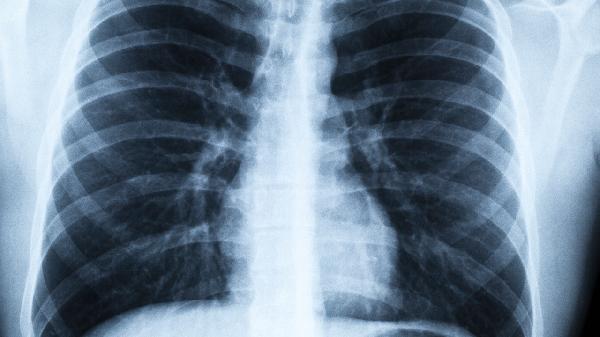

霧霾病引起的呼吸道疾病主要有上呼吸道感染、慢性支氣管炎、支氣管哮喘、慢性阻塞性肺疾病和肺癌。霧霾中的有害物質(zhì)可能刺激呼吸道黏膜,導(dǎo)致炎癥反應(yīng)或加重原有疾病。

長期暴露于霧霾環(huán)境可能導(dǎo)致支氣管黏膜反復(fù)炎癥,出現(xiàn)持續(xù)咳嗽、咳痰等癥狀。霧霾中PM2.5可沉積在細(xì)小支氣管,誘發(fā)黏液分泌增多。治療可遵醫(yī)囑使用鹽酸氨溴索口服溶液、乙酰半胱氨酸顆粒等祛痰藥物,配合布地奈德福莫特羅粉吸入劑控制炎癥。

霧霾會(huì)加速肺功能下降,加重COPD患者呼吸困難、咳痰等癥狀。PM2.5可引發(fā)肺泡結(jié)構(gòu)破壞,導(dǎo)致肺氣腫進(jìn)展。臨床常用噻托溴銨粉吸入劑改善通氣,配合多索茶堿片緩解癥狀?;颊邞?yīng)定期監(jiān)測(cè)肺功能并接種流感疫苗。

霧霾中含有的苯并芘、重金屬等致癌物質(zhì)長期吸入可能增加肺癌發(fā)病風(fēng)險(xiǎn)。這類物質(zhì)可導(dǎo)致支氣管上皮細(xì)胞DNA損傷,誘發(fā)惡性病變。對(duì)于高風(fēng)險(xiǎn)人群,建議每年進(jìn)行低劑量CT篩查,早期發(fā)現(xiàn)可通過手術(shù)或靶向治療如吉非替尼片干預(yù)。